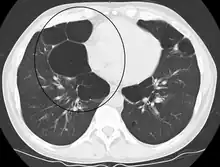

| Advanced centrilobular emphysema showing total lobule involvement on the left side | |

Centrilobular emphysema, also called centriacinar emphysema, affects the centre of a pulmonary lobule (centrilobular) in the lung, the area around the terminal bronchiole and the first respiratory bronchiole, and can be seen on imaging as an area around the tip of the visible pulmonary artery. Centrilobular emphysema is the most common type usually associated with smoking, and with chronic bronchitis.[17] The disease progresses from the centrilobular portion, leaving the lung parenchyma in the surrounding (perilobular) region preserved.[24] Usually the upper lobes of the lungs are affected.[17]